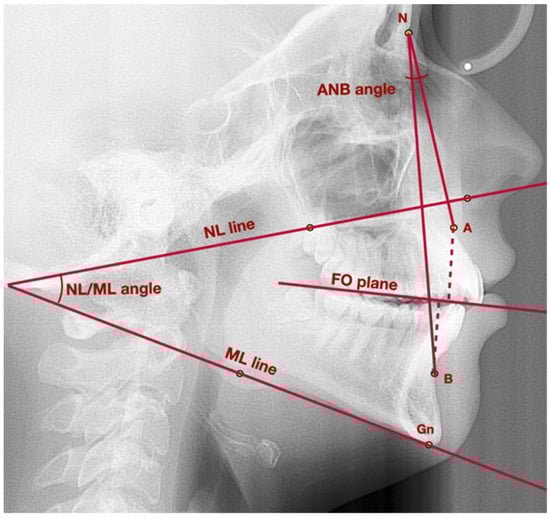

| General points and lines | Point A | Subspinale—point localized in the deepest area of the anterior outline of the maxilla, below the anterior nasal spine |

| Point B | Supramentale—point localized in the deepest area of the anterior outline of the mandible, above the pogonion | |

| Point S | Sella—geometrical center of Sella turcica | |

| Point Pg | Pogonion—the most prominent point localized in the mental tuberosity | |

| Point N | Nasion—the most anterior point localized in the frontonasal suture | |

| NL line | Nasal line—line which crosses the points: anterior nasal spine and posterior nasal spine | |

| ML line | Mandibular line—line tangent to the lower border of the mandible, which crosses points: gnathion and the lowest point in the masseteric tuberosity | |

| NA line | Line which crosses points: nasion and point A | |

| NB line | Line which crosses points: nasion and point B | |

| Vertical position of mandible | NL-ML angle | The angle between NL line and ML line |

| Sagittal position of mandible | Wits | The distance between the perpendicular projection of points A and B onto the functional occlusal plane |

| ANB | The angle between the lines: NA line and NB line | |